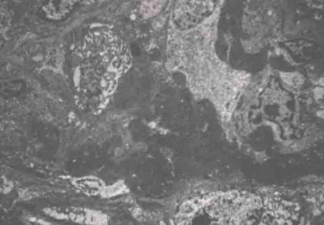

辅助检查:借阅外院肾活检病理:免疫荧光IgG(++),IgA(-),IgM(±),C3(+),FRA(-),C1q(-),沿毛细血管壁粗线样沉积(图1)。光镜可见23个肾小球,毛细血管袢严重破坏,伴多数新月体形成,9个细胞性、1个细胞纤维性新月体,1个节段性坏死。肾小管上皮颗粒及空泡变性,多灶状萎缩,肾间质多灶状淋巴单核浸润伴纤维化,小动脉管壁增厚(图2)。结合荧光考虑新月体性肾炎Ⅰ型可能性大。电镜:肾小球基底膜轻度增厚,上皮下电子致密物沉积,上皮细胞足突融合,肾小管上皮细胞溶酶体增多,灶状萎缩,肾间质淋巴单核细胞浸润(图3),符合Ⅰ期膜性肾病。

图2